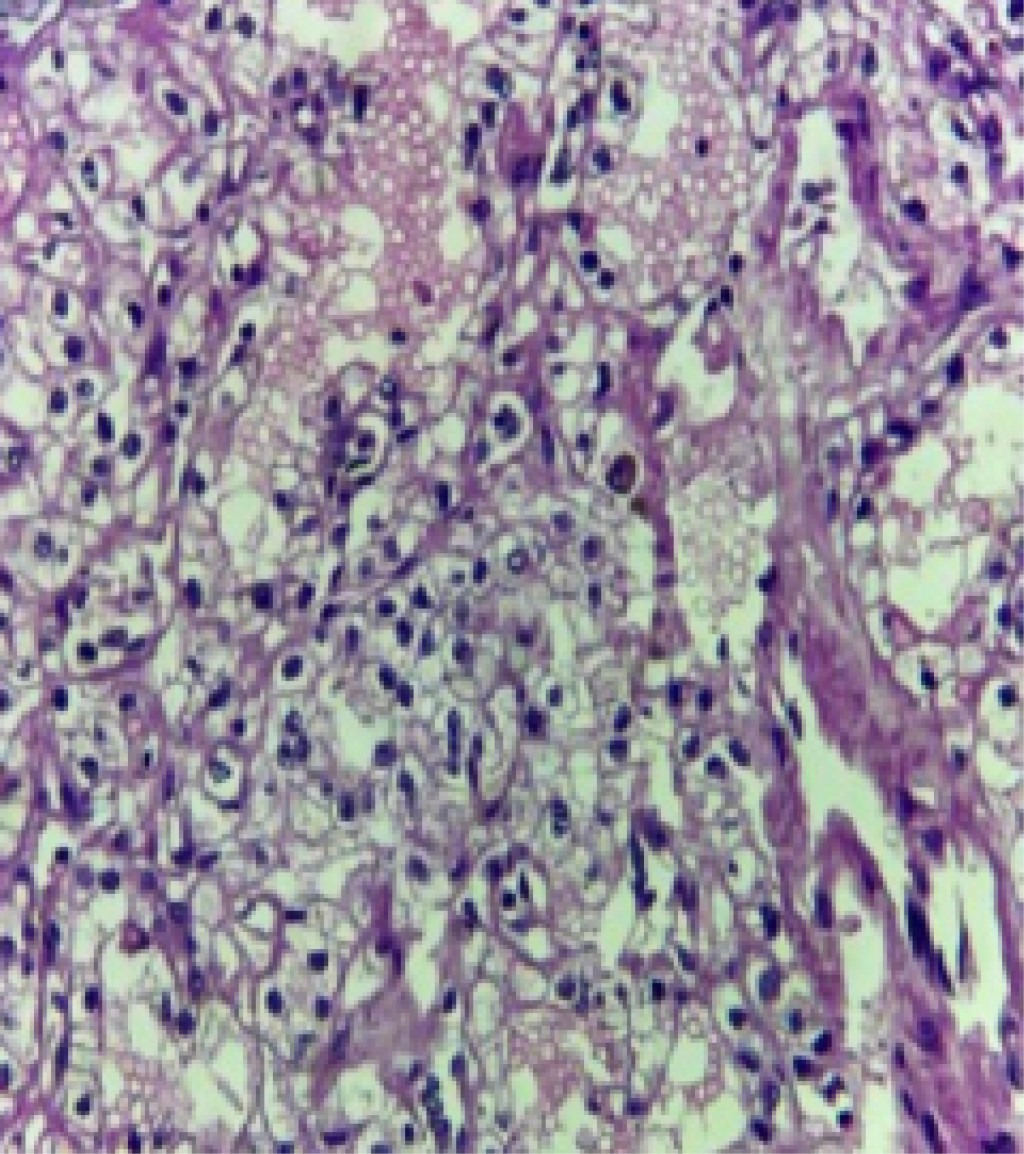

Figure 3